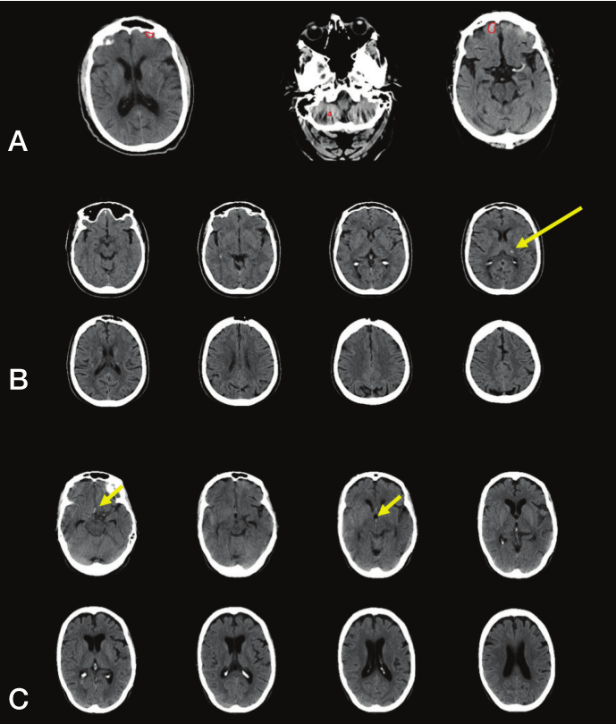

RAPID ICH准确识别151/158例ICH+病例和143/150例ICH-病例。RAPID ICH检测脑出血具有较高的敏感性(0.956;95% CI,0.911-0.978)、特异性(0.953;95% CI,0.907-0.977)、阳性预测值(0.956;95% CI,0.911-0.978)和净现值(0.953;95% CI,0.907-0.977)。NCCT影像中,RAPID ICH检测未发现出血(假阴性)病例的脑出血体积较小(1.5mL)和位于脑实质内、脑室内和硬膜下(图1)。

图1. RAPID ICH假阳性和假阴性的NCCT成像。A.RAPID ICH将前颅底骨质伪影误认为脑出血(红圈)--假阳性;B.RAPID ICH未发现左侧丘脑的少量出血(黄色箭头所指)--假阴性;C.RAPID ICH未发现少量蛛网膜下腔出血和脑室出血(黄色箭头所指)--假阴性。